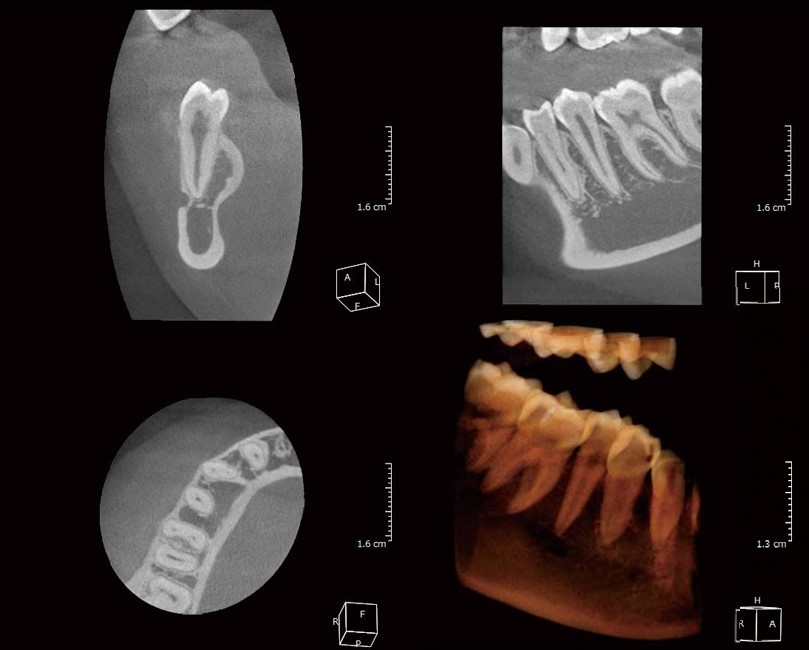

Hình ảnh chụp toàn hàm từ X-ERA Smart

- Cung cấp hình ảnh 2D hoặc 3D (tùy thiết bị) mang đến cho Bác Sĩ cái nhìn trực quan, rõ ràng.

Thiết kế nhỏ gọn và mỏng nhưng đầy đủ chức năng, X-ERA Smart là trợ thủ tốt nhất giúp Bác Sĩ quan sát được mô hình hình ảnh toàn cảnh/cephalometric 2D, 3D.